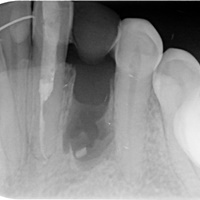

Po urwaniu narzędzia w zębie, endodonta odstąpił od leczenia kanałowego. Wykonano resekcję. Na RTG widoczne dobre gojenie tkanek kostnych, niewidoczna blizna na dziąśle.